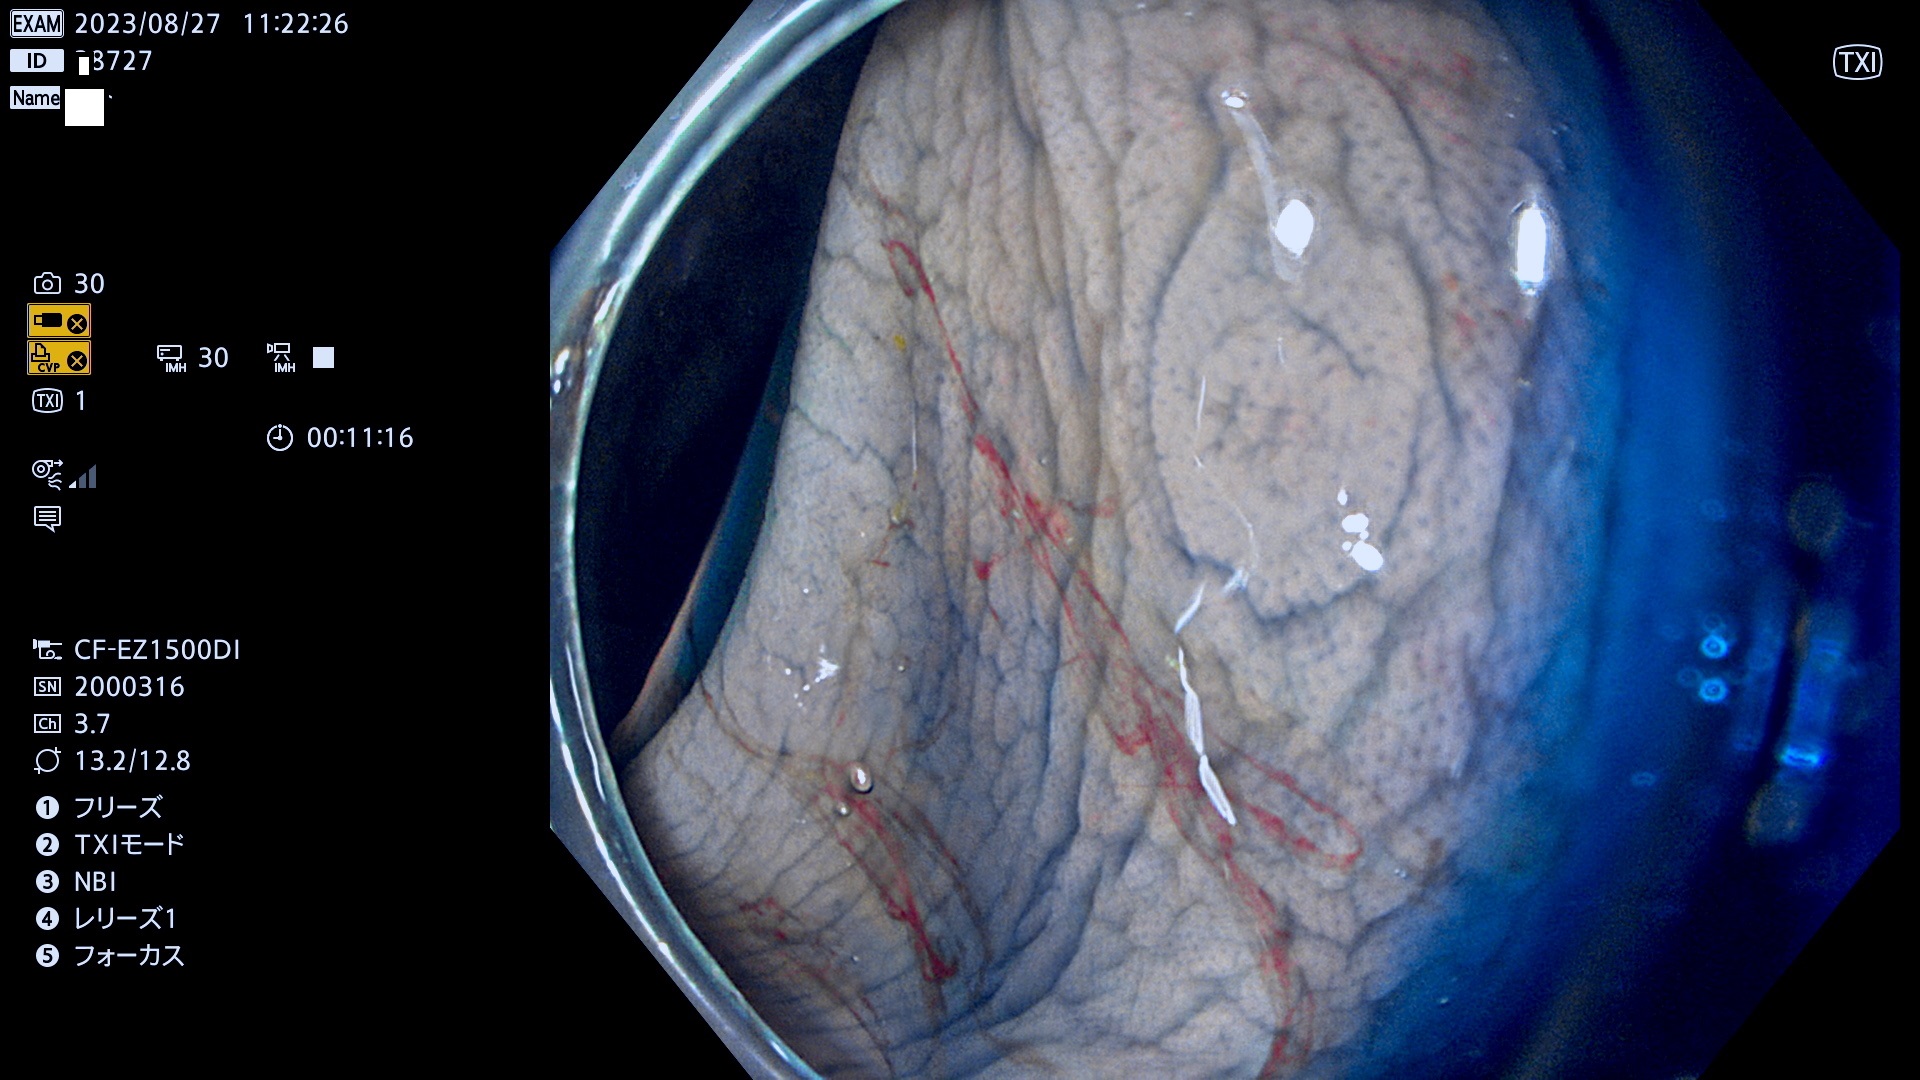

表面型腺腫(Flat Adenoma)の中で、完全に平坦な物をUb、陥凹している物をUcと呼びます。平坦隆起型(Ua)よりも、発見が難しく危険な病変です。このタイプは「内視鏡後・大腸癌の重要犯人」であり、この発見率は「腺腫発見率」よりも、重要な意味があります。

専門的)何故、陥凹していると危険? 癌遺伝子の変異が蓄積すると細胞分裂が盛んになり隆起するのでは?と通常は思われるでしょう。しかし実際は逆です。これは2022年の記事にある「細胞はストレスに直面したら細胞分裂を止める(細胞老化に入り休眠する)という生命の基本的現象」によるものです(Oncogene Stress)。細胞老化を起こすのが癌抑制遺伝子で、この安全装置(ブレーキ)が壊れると癌になります(休眠からの覚醒)。ですから陥凹は「まだ癌では無いが癌化の直前」を意味します。特に「小サイズなのに陥凹している」病変は短期間に腫瘍進化(⇒2021年記事)が起きたことを意味します(=ゲノム不安定性

毎週の検査(木・金・土・日)に発見されたUb、Uc型・腺腫を、その週の日曜の夜にUPし1週間、提示します。

抽出の対象期間 2023年8月24日(木)〜8月27(日)の4日間(48件の検査)9件